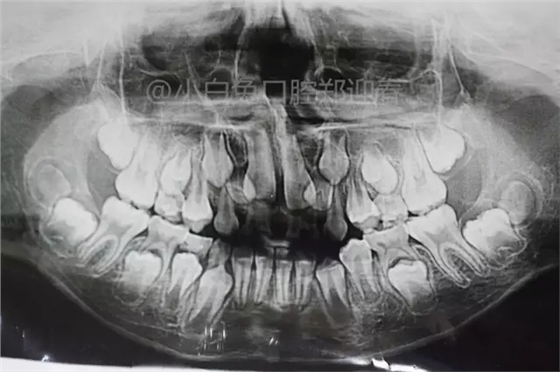

患兒,10歲,因上前牙未替換來診,查體:輕度反合,51和52、61和62均融合,且存在間隙約4mm,全面曲面斷層片顯示:11、21未萌,52、51、61、62牙根均有不同程度的生理性吸收。

8、乳牙融合牙作X線片檢查時(shí),會(huì)發(fā)現(xiàn)大部分的乳牙融合牙缺失一個(gè)后繼恒牙的牙胚,如乳牙為下頜乳側(cè)切牙和乳尖牙之融合,在其根端應(yīng)當(dāng)有恒牙的側(cè)切牙和尖牙的牙胚,但往往缺一個(gè)恒牙牙胚。而且不論是乳側(cè)切牙和乳尖牙之融合或是乳中切牙和乳側(cè)切牙的融合,所缺的后繼牙牙胚都是恒側(cè)切牙,這可能與恒牙先天性個(gè)別牙缺失中多見于下頜側(cè)切牙有關(guān)。由于融合后的這兩個(gè)雙牙畸形牙,它的牙冠寬度小于兩個(gè)牙的牙冠寬度之和,而影響牙列的大小,尤其在雙側(cè)性乳牙融合牙,對(duì)牙列大小的影響尤大。